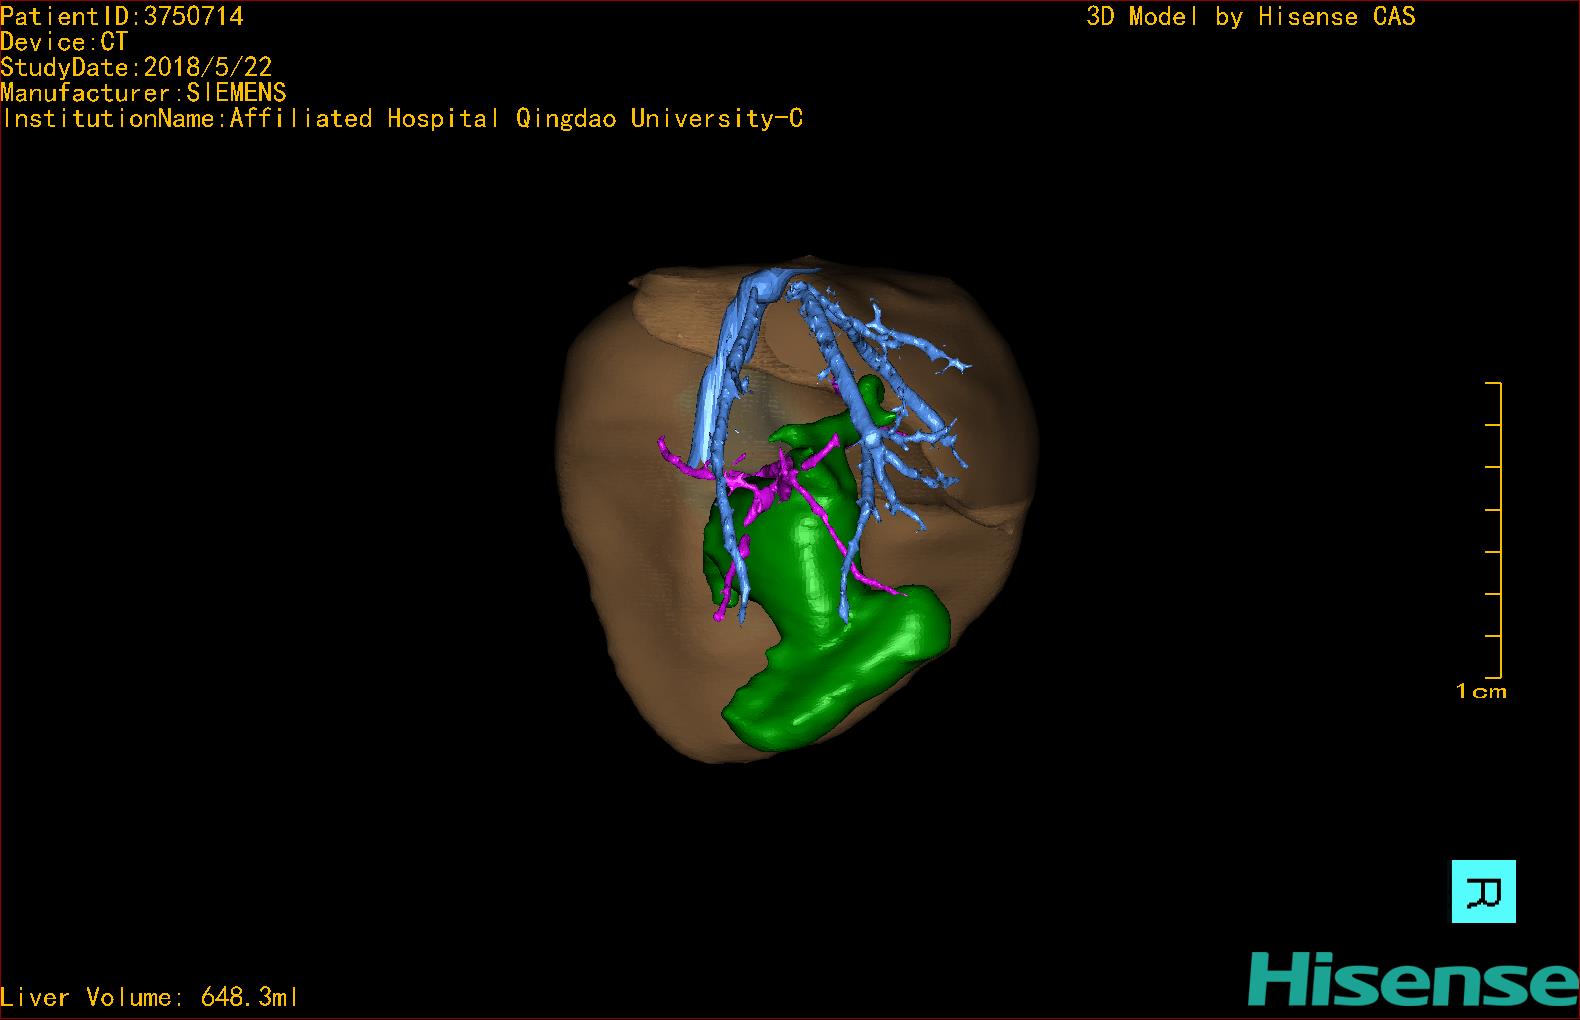

实验室检查: 血常规:WBC 16.16*109/L,NEU2.88*109/L,RBC3.76 1012/L,HB 92g/L, PLT 414*109/L 生化全套:ALT 50.00 U/L, AST 147.00 U/L, ALT/AST 0.34,LDH 367.00 U/L, ALB 36.91g/L, GGT 1297.00 U/L, ALP 1155.00 U/L, BIL-T 138.23 umol/L, BIT-D 97.01 umol/L, TBA 48.40umol/L,ADA 40.00U/L, PAB 121.40mg/L, BUN 1.98 mmol/L, CREA 17.00 umol/L 肝炎全套: 炎症反应标志物:CRP 7.27mg/l 诊疗过程: CT结果输入海信CAS系统后行3D重建及手术规划后,于2018-5-31全麻下行“胆总管囊肿切除+肝总管空肠吻合术”手术治疗: 术前三维重建及手术方案设计: 将0.625mm双源薄层CT资料的静脉期和动脉期Dicom格式文件导入海信CAS系统。 通过调节窗宽窗位调整CT序号,对肝实质,胆囊,下腔静脉,肿瘤,肝动脉、门静脉及肝静脉等进行三维重建;系统自动计算肝脏体积,肝脏体积为648.3ml,通过术前模拟手术,精准判断手术切除范围,进行精密术前规划及讨论后实施手术。 手术步骤: 麻醉成功后,患儿取平卧位,2.5%碘伏消毒手术区皮肤,铺无菌巾单。取右上腹纵口长约5m,切开皮肤、皮下织组,腹直肌前鞘、腹直肌,后鞘和腹膜。探查见:胆总管3×2cm大小,胆囊管迂曲,长约10cm。 剥离、切除胆囊,游离胆总管,将之横断:①近端即肝总管,剪裁后被吻合用;②远端游离切除囊肿内壁,直至胆总管开口于十二指肠处,冲洗后予以结扎缝扎。距treits韧带20cm处横断空肠:①近端与其远端25cm处的空肠侧壁行端侧双层吻合,吻合口通畅;②远端断端封闭,其侧壁剪开,并经横结肠后提至肝门处,与剪裁的肝总管行端侧双层吻合。缝合修补胆囊床及系膜裂孔,肝门部放置橡胶引流管一根。温盐水冲洗腹腔。检查无活动性出血,清点纱布器械无误,依次缝合腹壁各层。手术顺利,麻醉满意,出血不多,未输血,术后病人先进入麻醉恢复室,苏醒后回病房。手术时术者可开启Hisense CAS系统手势控制功能,对肝脏及胆囊解剖结构进行实时、全方观察、评估,起到术中导航作用。 术后病理: 1. (囊肿壁)囊肿性病变,囊壁部分区域衬覆柱状上皮。 2. 慢性胆囊炎。 3. 送检(肝门)淋巴结查见淋巴结1枚,呈反应性增生。 随访情况: 患儿术后2周恢复良好 术前CT检查:动脉期

术前三维重建:重建图片.jpg)